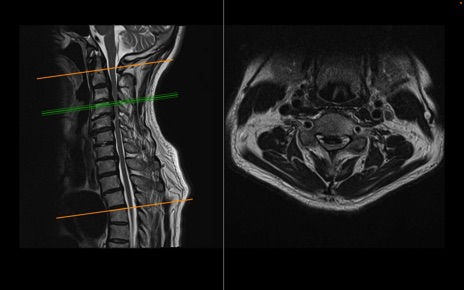

頚椎MRI

T2WI(横断像)

T2WI(矢状断像)